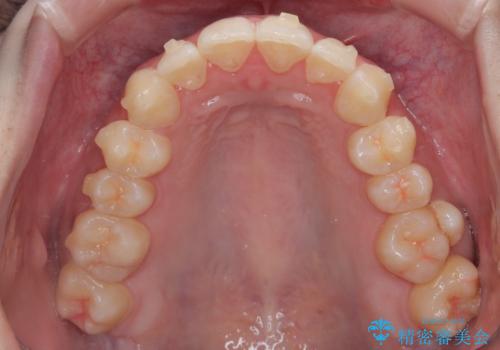

診察してみると、下の前歯が並ぶためのスペースが足りないことが、歯並びがデコボコしている原因でした。

そこで今回は、以下の2つの方法を組み合わせて治療を行いました:

下の前歯の歯と歯の間をわずかに削ってスペースを作る(IPR)

奥歯を後ろに動かして、前歯が並ぶためのスペースを確保する

この計画により、デコボコだった下の前歯はしっかりと並び、わずか1年で治療を終えることができました